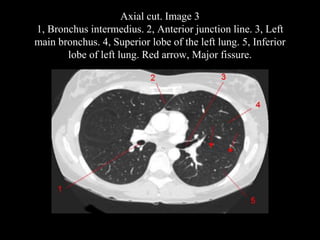

The document discusses the anatomy of the chest x-ray and CT scan by describing the lobes of the lungs and their locations. It also mentions the heart, mediastinum, hilum, and ribs. Several axial, coronal, and sagittal CT images are included with labels pointing out structures like the trachea, bronchi, lobes of the lungs, and fissures. In summary, the document provides an overview of lung and chest anatomy as seen on x-rays and CT scans through text descriptions and labeled medical images.